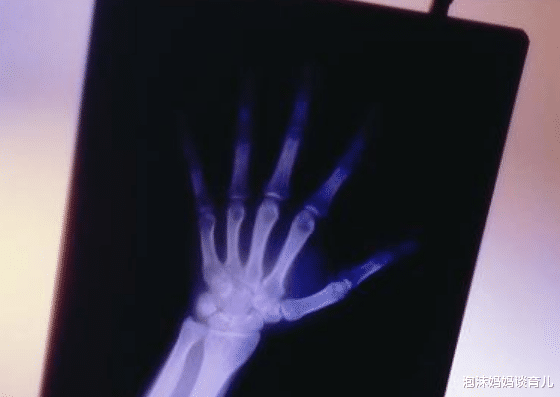

除了WIFI之外 , 还有哪些辐射会对孕妇造成影响?1.X光

孕妇没有特殊情况 , 千万不要到医院去做一次X光片 , 其中的辐射对正常人来说都是很大的 , 更何况孕妇 , 如果没有必要去拍片的情况下 , 孕妇要远离医院 , 有X光辐射的地方 , 也要做好防护 。